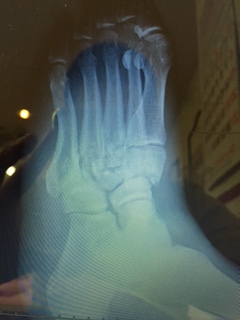

接骨院ではレントゲン撮影やMRIなどの画像診断は出来ず、 鑑別の必要な症状であれば接骨院近くの病院やご自宅近くの病院へ ご紹介させていただきます。

場合によってはレントゲン写真をDiscにしていただくこともあ りますが、 私たち柔道整復師はレントゲン写真の評価も出来ますので安心して お預けいただければと思います。